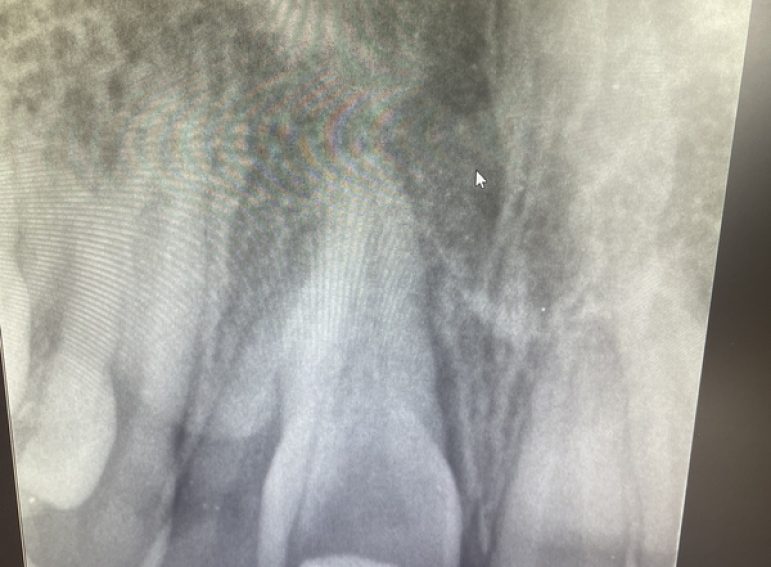

Surgical management of external cervical resorption.